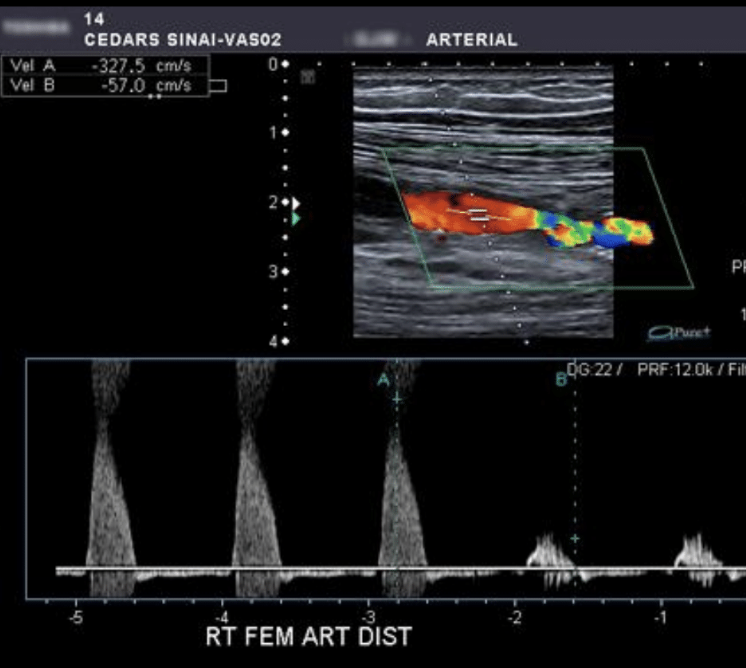

¿Onda anormal o trifásica?

Anormal

Hallazgos de doppler arterial

Placas de ateroma

Ausencia ed flujo

Cambios en la onda